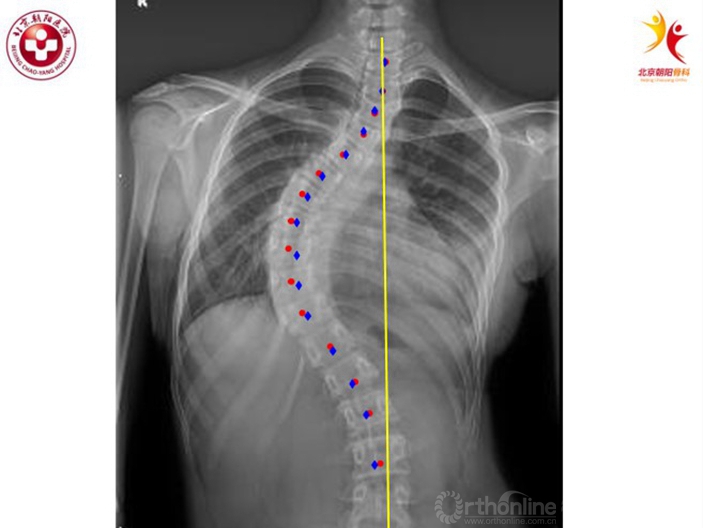

简单的解释骨生长不协调,或者说是神经、骨骼生长失平衡的结果。下图红色的点是椎体中点,蓝色的点为双侧椎弓根的中点,多数AIS患者都存在不同程度的顶椎旋转,在X光片上,由于存在旋转,椎体的中心会比椎弓根的中心更偏离中线。如果将红点和蓝点各自连起来,直观的看红线长于蓝线,也可以说在部分AIS患者中脊柱前方的结构总长度要长于后方的结构。

图12